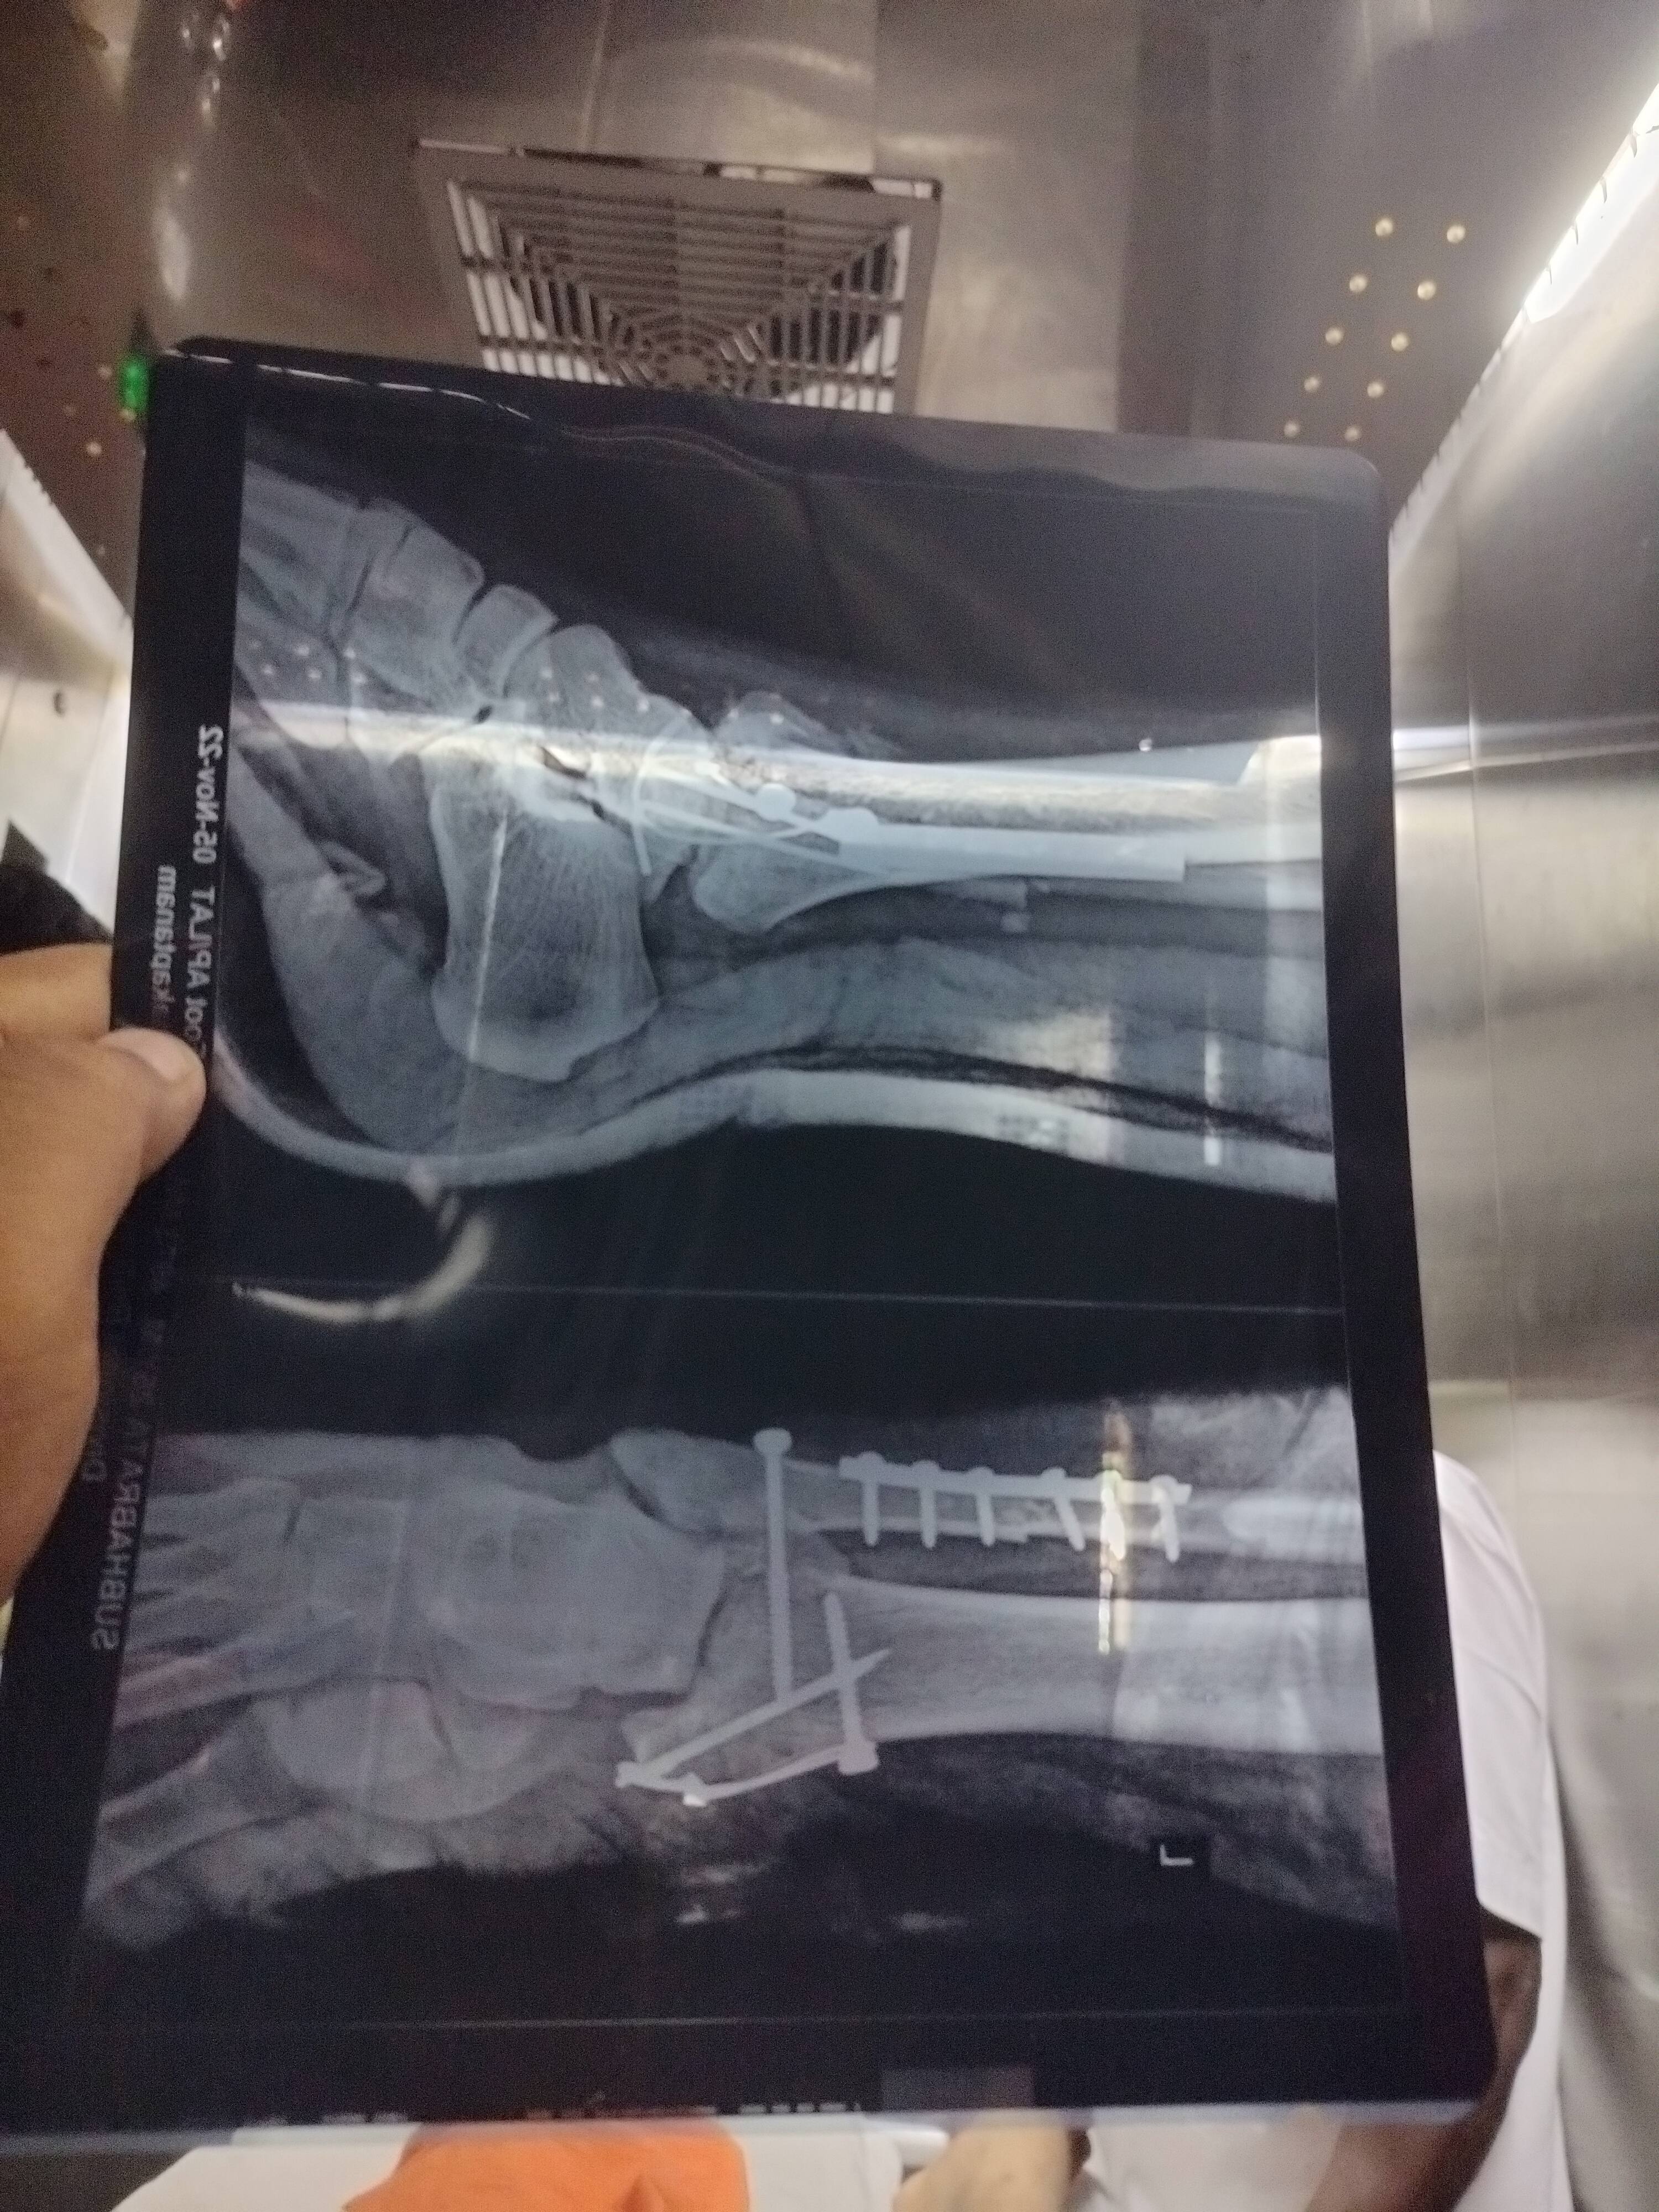

Sir weather my surgery was fine.post one month swelling reduce but when i walk with Walker by non weight bearing on one leg swelling seen . Pain is negligible. Weather everything going good with me and the surgery done correctly or not sir.